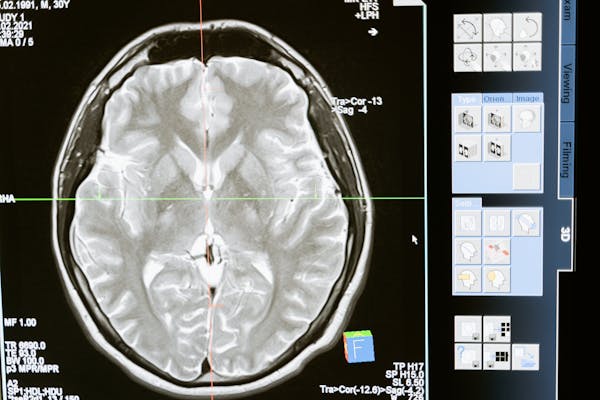

인지행동치료(Cognitive Behavioral Therapy, CBT)는 부정적인 사고 패턴과 행동을 변화시켜 정신 건강을 개선하는 데 효과적인 심리치료법입니다. 최근 10년간의 뇌과학 연구는 CBT가 단순히 증상 완화를 넘어 뇌의 구조와 기능을 재구성하는 신경가소성 변화를 유발한다는 것을 입증했습니다. 아래에서는 CBT가 뇌에 미치는 영향을 영역별, 네트워크별로 분석하고 그 임상적 의미를 설명합니다.

CBT는 단기적 증상 완화뿐만 아니라 뇌의 구조적 재구성을 유도합니다. 해마의 신경 발생 촉진, 전전두엽의 회백질 밀도 증가, 편도체의 부피 감소 등이 보고되었습니다.

CBT의 신경과학적 효과는 개인 맞춤형 치료 전략 개발에 기여합니다. 예를 들어, fMRI를 활용해 전전두엽-편도체 연결성을 모니터링하면 치료 반응을 예측할 수 있습니다. 또한 디지털 CBT 앱과 뉴로피드백을 결합하여 뇌 활동을 실시간으로 조절하는 연구가 활발히 진행 중입니다.

CBT는 뇌의 기능적 네트워크(전전두엽, 편도체, ACC)와 구조적 변화(회백질 밀도, 부피)를 통해 정신 건강을 개선합니다. 이는 CBT가 단순히 행동 수정을 넘어 뇌의 생물학적 변화를 유도하는 종합적 치료법임을 의미합니다. 향후 뇌영상 기술과의 융합을 통해 더욱 정밀하고 효과적인 치료 프로토콜이 개발될 것으로 기대됩니다.